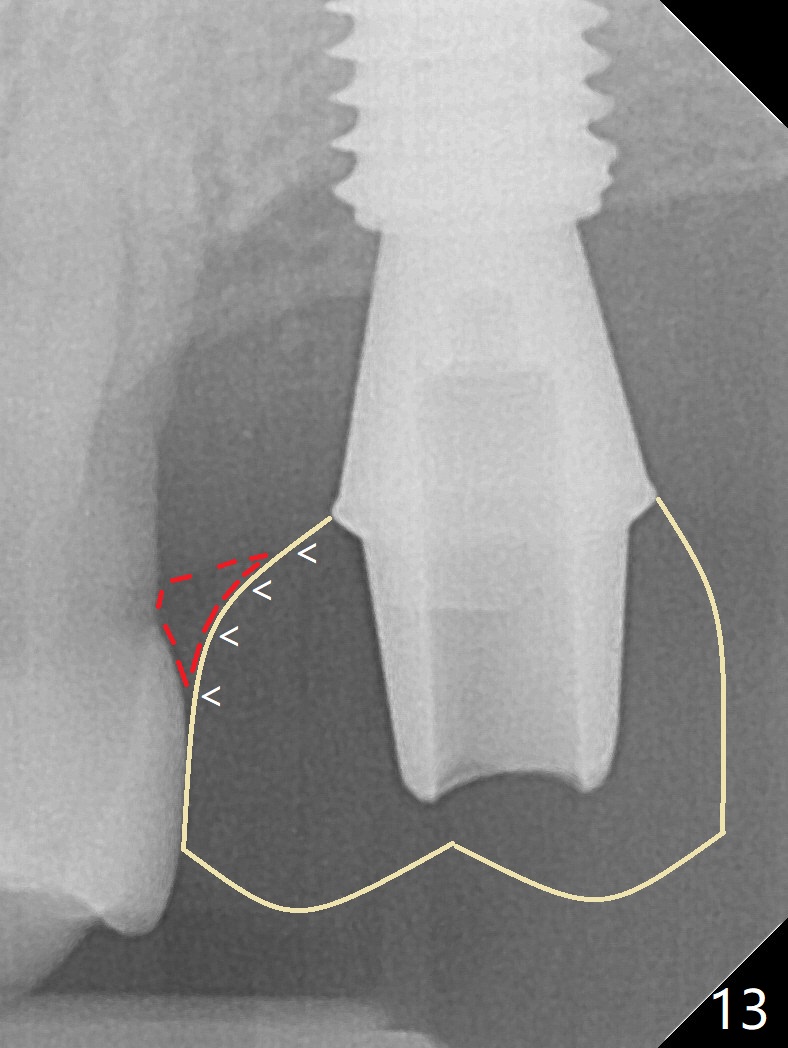

Although the buccal (Fig.1 (mesial view of the extracted tooth #15): B) root is larger than the palatal (P) one, the palatal socket is larger than the buccal one (Fig.2 white area) because of the bone loss of the former. For better restoration, osteotomy (Fig.2 red line) is initiated in the buccal slope of the septum (S) so that the final osteotomy is in the middle of the whole socket (Fig.3 red box). In fact a 3 mm stopper is not used because of the slope and the clumsy stopper. Stopper would be indicated if the bottom of the bone were flat. At first a 4x10 mm dummy implant is placed with stability (Fig.4). After further osteotomy and sinus lift (Fig.6 red dashed line: sinus floor), a 5x10 mm implant is placed with 30 Ncm, followed by insertion of a 5.2x8(2) mm temporary abutment (Fig.5,6). The latter holds an immediate provisional and Vanilla Graft/Osteogen (Fig.7 *) in place (^: distal crestal bone). Although the bone looks normal around the implant 7.5 months postop (Fig.4), the implant is unstable, probably due to the large preexisting defect. In contrast the implant placed at the healed site of #3 is stable 6.5 months postop. The 8x5 mm healing abutment that dislodged for 1 day could not return. A 6x5 mm one is used; it appears that the bone density mesial and distal to the implant is low (Fig.9 *). The implant looks normal and is stable 13 months postop (Fig.10). A 5.7x5.5(5) mm cementation abutment is placed for a provisional (progressive loading, Fig.11). There is no pain associated with the provisional for mastication. Impression is taken 7 days later. The patient has pain when the permanent crown is cemented. It appears that the implant does not osteointegrate and should be removed. A 6x14 mm tissue-level implant will be immediately placed following a 5 and 6x14 mm taps and bone graft and PRF (Metronidazole). In fact there is no pain when the existing abutment is torqued at 35 Ncm 1 year 8 months postop (Fig.12). The mesiogingival portion of final restoration (Fig.13 arrowheads) should be bulky so that the gingival embrasure (red dashed line) is minimal to reduce food impaction.